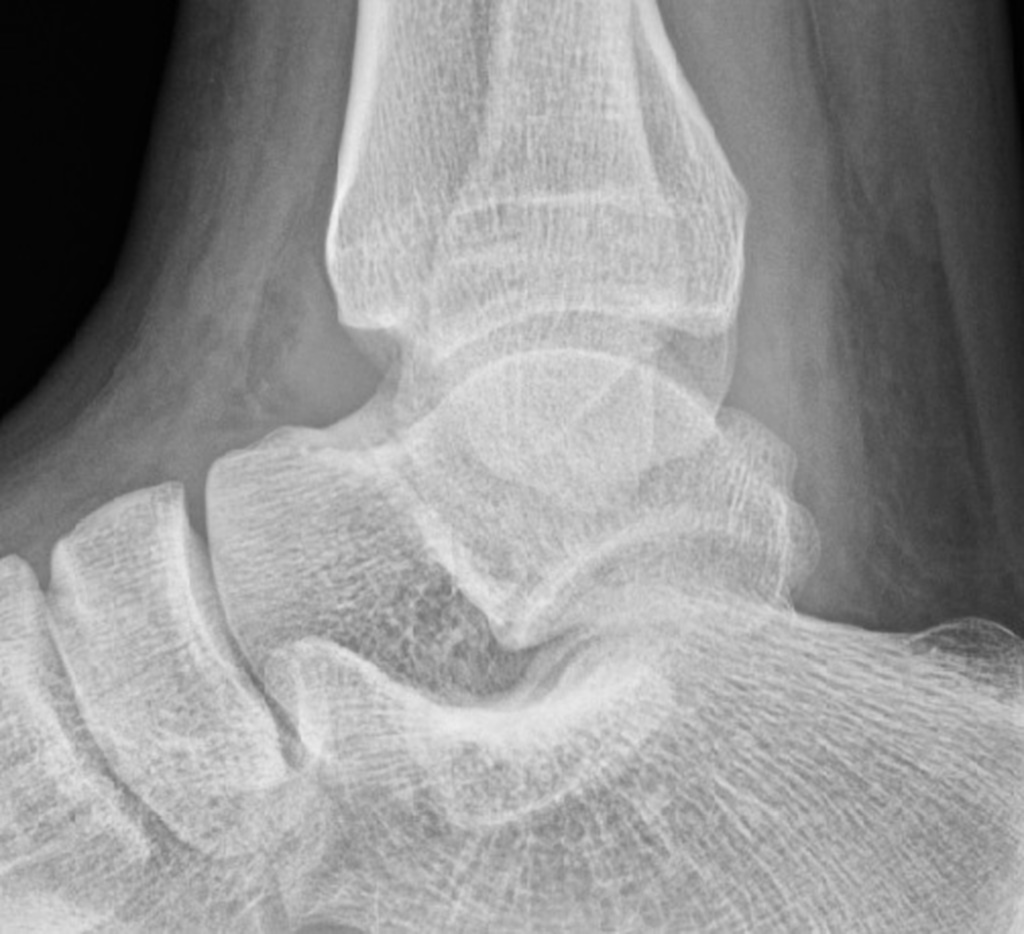

When the joint capsule is expanded by the effusion, the adjacent fat planes are displaced and we see the now familiar, slightly radiopaque culprits. Filling of the posterior recess is poorly appreciated on radiographs due to overlying bony anatomy, therefore looking within the anterior recess for what is known as the “teardrop sign”, a grossly ovoid opacity obscuring or distorting the anterior fat pad, is what will give us our diagnosis of ankle joint effusion.

As with any other effusion, this sign is non-specific and doesn’t indicate any particular pathology by itself. Clinical context is important. If the patient has presented with history of trauma, has clinical signs indicating a potential fracture and an effusion is seen with no appreciable bony injury then consider repeat imaging (if non-standard views have been obtained), additional views (if allowed by local protocol) or potentially cross-sectional imaging if index of suspicion is high.